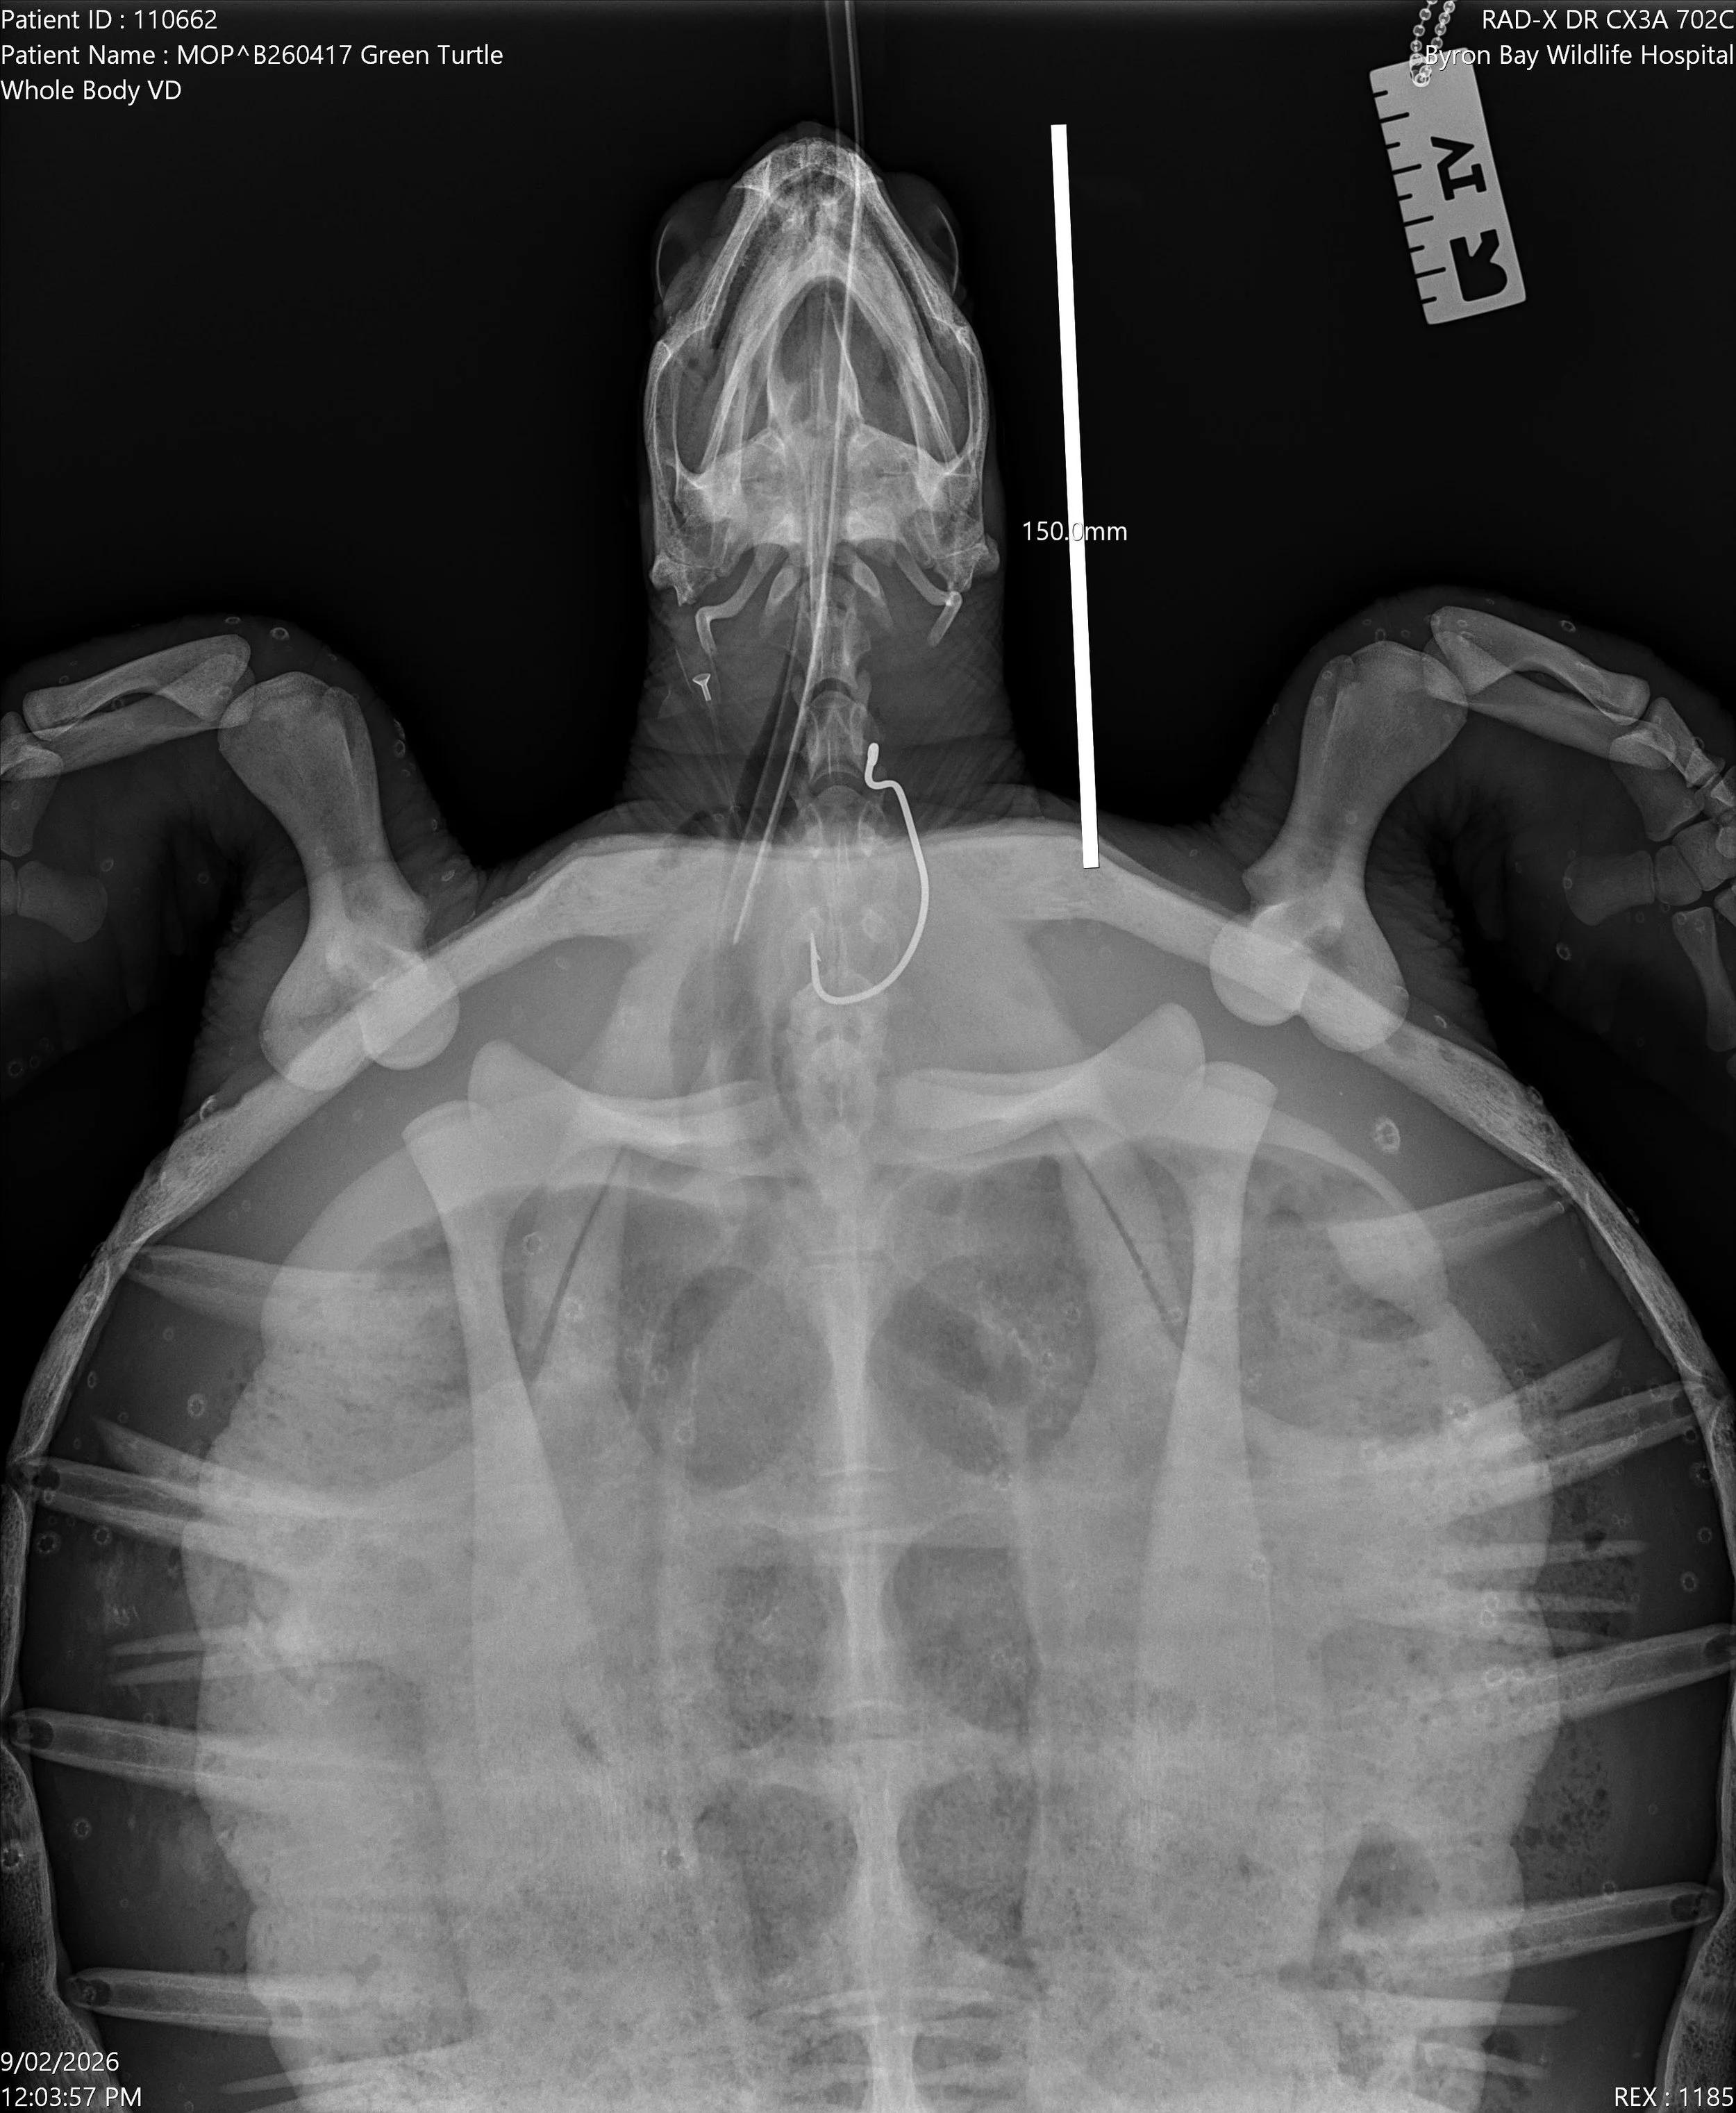

Pickles the green sea Turtle

Our rescuer was phoned on our Rescue Hotline about a turtle that had been hooked while a member of the public was fishing. Two divers were there and were able to retrieve Pickles from the water - thankfully, because if the fishing line had been cut to set the turtle free, he would have swum away with a huge hook in his throat and would have died a slow and painful death. He was sent to Byron Bay Wildlife Hospital to have the hook surgically removed. Luckily, the hook was removed successfully, but he now has a long road to recovery. A case like this could take anywhere from 4–6 months of rehabilitation. Pickles was not unwell, had no other injuries and was otherwise in good health. He shouldn’t be in care, but we will give him all the TLC he needs.